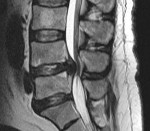

Люмбальную или субокципитальную пункцию совмещают с проведением соответственно восходящей или нисходящей миелографии. Последняя выявляет экстрадуральное (частичное или полное) сдавление спинного мозга, однако малоинформативна в отношении дифференциации вызвавшего компрессию объемного образования, не может различить абсцесс, гематому и опухоль спинного мозга. Наиболее надежным и безопасным способом диагностировать спинальный субдуральный абсцесс является проведение КТ, оптимально - МРТ позвоночника.